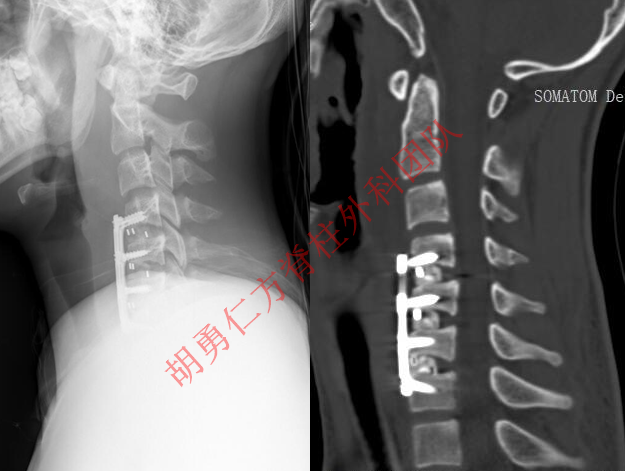

平山病